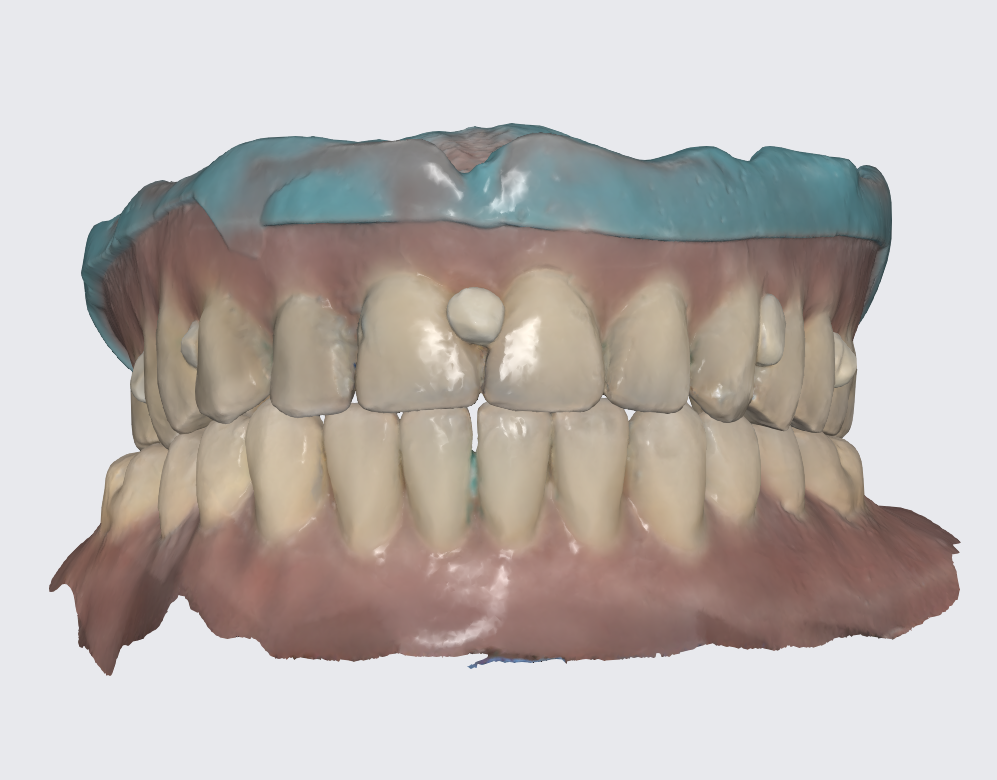

To prepare for the maxillary all on X procedure patient had the upper denture relined with impression material and also multiple dots of radio opaque filling material where temporarily placed on the said denture. Then the 2 dentures where scanned. Also scans of the healed tissues and of the face where recorded.

Using the Aoralscan Elite intraoral scanner (Shining 3D), detailed scans of edentulous ridges and interim prostheses were recorded efficiently and accurately. Edentulous arch scanning proved precise and rapid, significantly simplifying the workflow.

Shining 3D Metismile face scanner was used to perform the face scan and also alignment of intra oral data with the said face mesh. With the new updates teeth color is corrected on the intra oral scan to match the one recorded by the Metismile so that a more coherent look can be generated. Lip contour was automatically removed from the face scan after data matching.

A new waxup was generated in Exocad and printed as a try in to check occlusion but also esthetics at some degree and have a proprosthetic implant positioning available in the planning step.